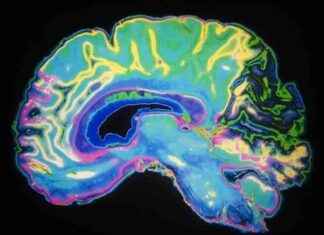

Yeni Bakış Açılarıyla Parkinson Hastalığı Hastalarında Kontrolsüz Hareketler Yeni Araştırma Parkinson Hastaları İçin Umut Verici Keşifler Ortaya Koydu Parkinson hastalığı, beyindeki bir nörolojik bozukluk olup, kişinin hareketlerini etkiler. Beyindeki bir kimyasal olan dopamin seviyesi azaldığında Parkinson...